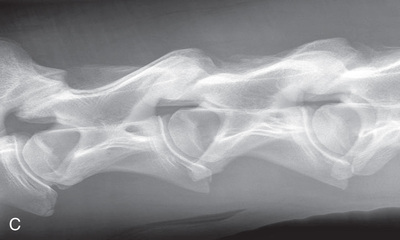

| Thoracic spine | Lateral (Fig. 24.59) | Side of the patient on area of interest. | Opposite side. | Area of interest perpendicular to the image receptor. | Often completed for the dorsal spinous processes (withers). |